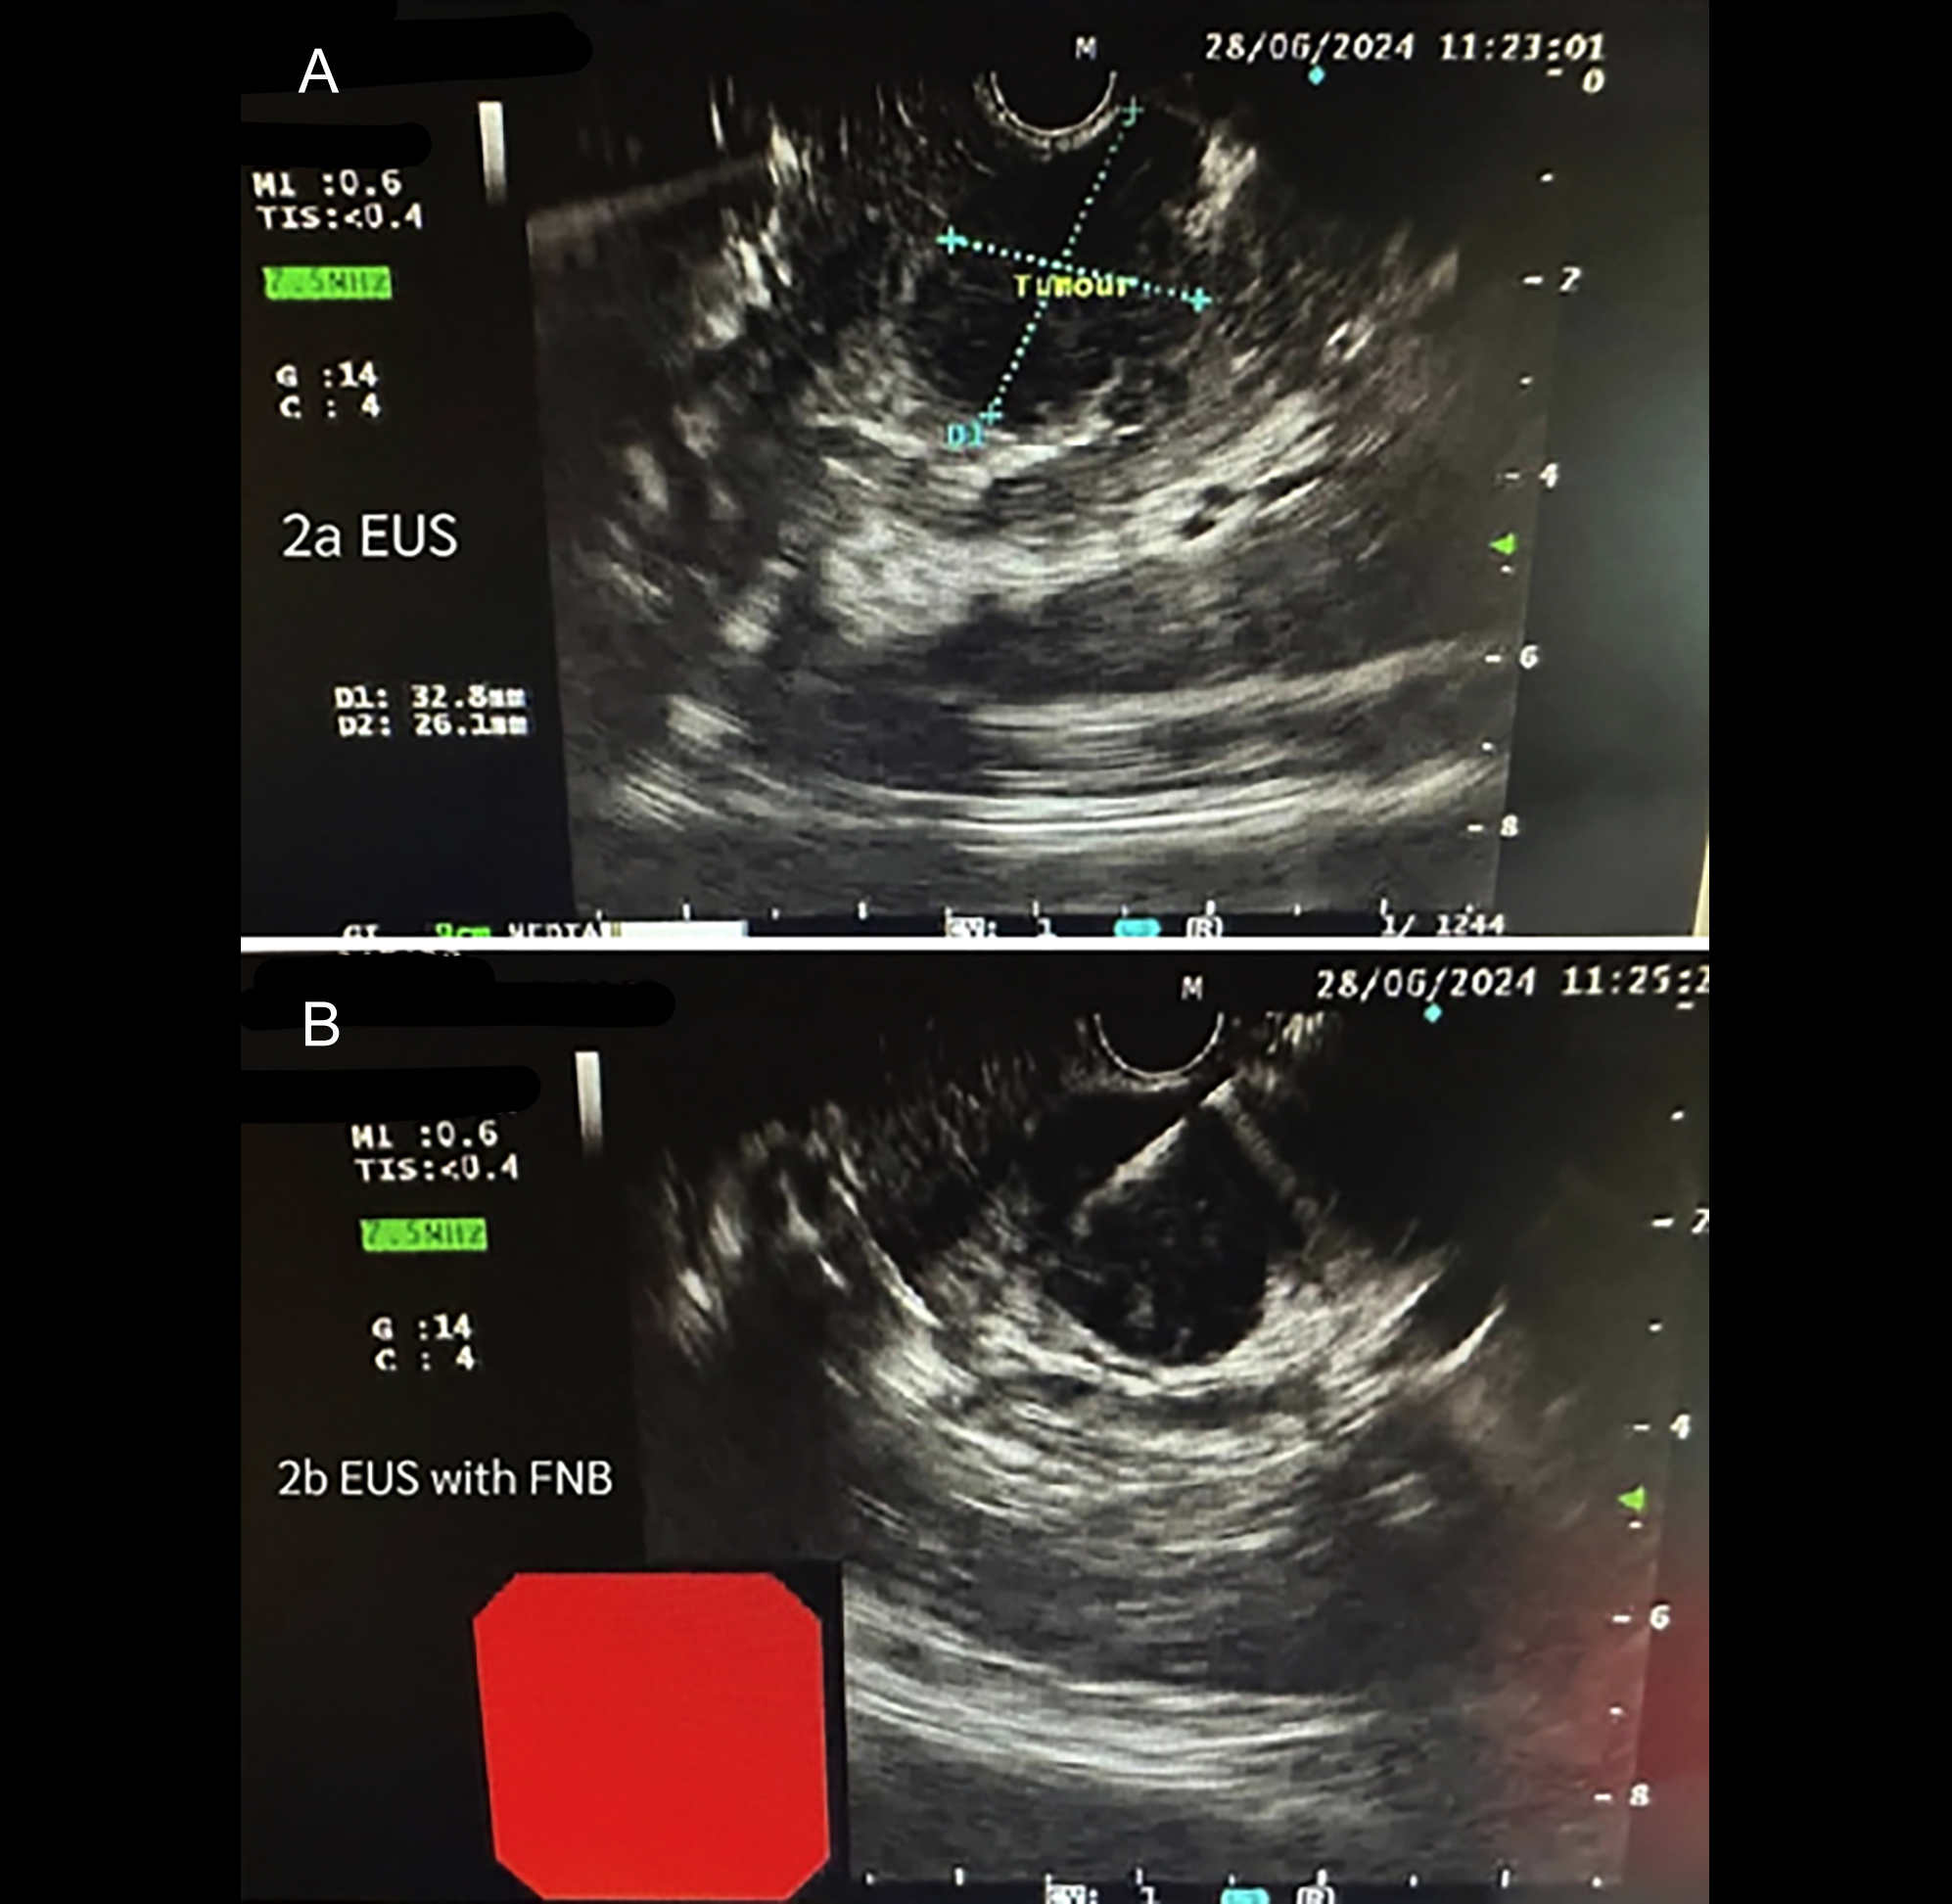

The clinical examination was normal with no visceromegaly or lymphadenopathy. The initial work-up revealed a drop in haemoglobin to 11 g/dl from 15.5 g/dl, reported 3 months before the onset of fever with a normochromic normocytic picture on peripheral smear. Total leucocyte count (TLC) and platelets were in the normal range. Liver function tests, renal profile, and thyroid profile were normal. The blood culture was also negative. However, on ultrasound abdomen, a solid-looking and well-defined mass of 3.5 × 2.3 × 1.7 cm was noted in the head and neck of the pancreas. Abdominal CT scan revealed a multiseptated mixed consistency lesion of 3.5 × 3.1 cm in the pancreatic body projecting in the gastro-hepatic recess, closely abutting adjacent hepatic capsule with marginal neovascularity, and prominent aortocaval necrotic lymph nodes. No visceral metastasis was identified (Figure 1). The patient was listed for an EUS examination. The presence of a heterogenous lesion adjacent to the pancreatic neck was confirmed with no vascular involvement and fine needle aspiration cytology (FNAC) was obtained for diagnosis (Figure 2). Cytology of FNAC sample revealed aggregates of epithelioid histiocytes and few lymphocytes with necrosis suggestive of caseating granuloma. Mycobacterium Tuberculosis was isolated in culture after three weeks. The patient was started on anti-tuberculous medications and his symptoms settled two weeks after starting treatment. He is on regular follow-up in outpatient clinic for compliance and continuation of treatment for one year.

Figure 2: (A) Pancreatic mass on endoscopic ultrasound (EUS). (B) Fine needle aspiration cytology (FNAC) being performed.